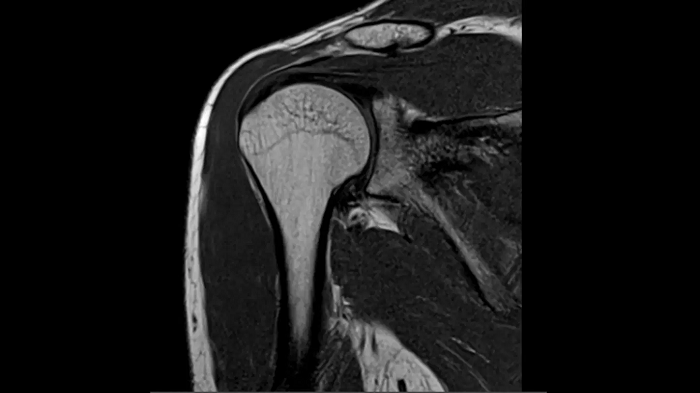

Shoulder

T1 TSE with Deep Resolve and Simultaneous Multi-Slice

Outstanding T1 imaging of the shoulder using MAGNETOM Free.Star. Integrating the Deep Resolve’s power with the proven Simultaneous Multi-Slice technique.

SMS 2 | Deep Resolve Gain & Sharp

0.4 x 0.4 x 3.0 mm2

TA 3:37 minutes

MAC-ID: 7aaaa0213.

MAC-ID: 7aaaa0213. Image Credit: Siemens Healthineers